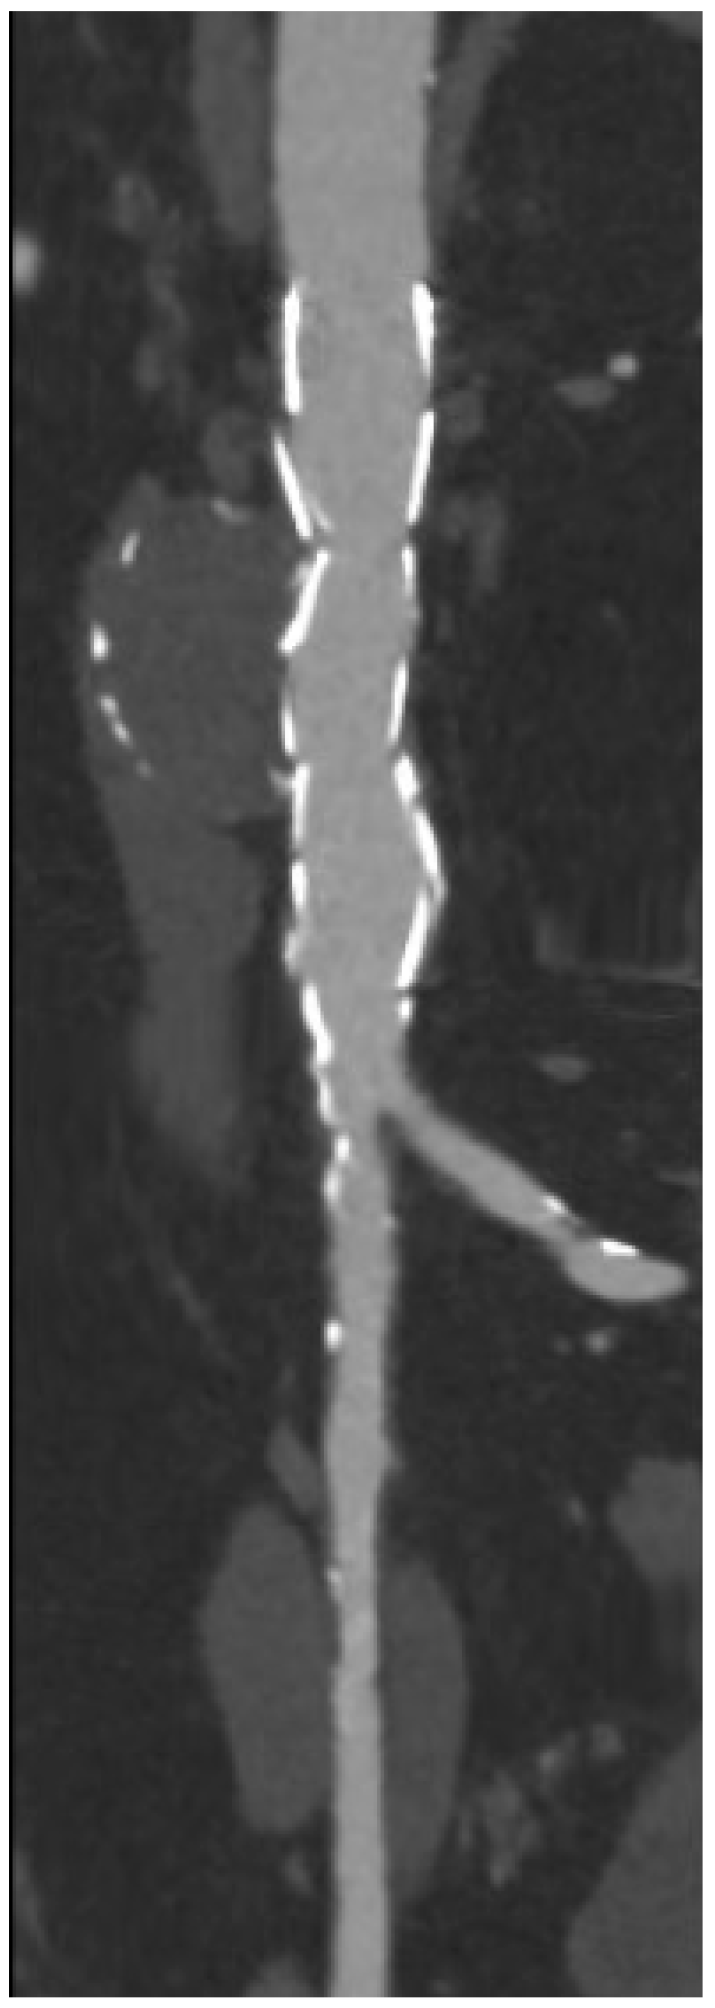

4.1. Infrarenal EVAR